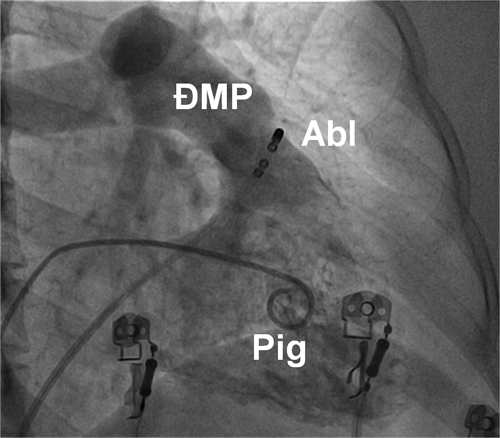

Hình 14: Vị trí các ống thông trên hình ảnh X quang trong triệt đốt ngoại tâm thu thất khởi phát từ đường ra thất phải trên góc nghiêng phải 30 độ: Pig: ống thông Pigtail chụp buồng thất phải, Abl: điện cực triệt đốt được đưa vào vùng đường ra thất phải, ngay dưới van động mạch phổi